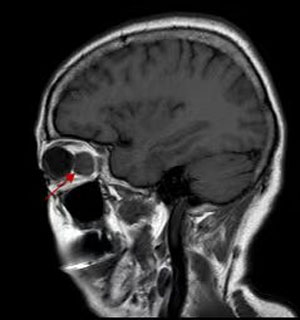

B超、CT、核磁共振等影像學檢查都必不可少,可以提供病變的位置、大小。細針穿刺活檢創傷小,但可以獲取細胞學標本,幫助診斷。有的病例需要手術活檢進行病理檢查明確診斷,指導治療。

就腫瘤而言,手術完整摘除是最常用的治療手段,由于在眼眶有限的空間內,集中了眼球、視神經、眼外肌、供養血管等重要結構,因此手術是有難度的。醫生根據眼眶腫瘤的位置選擇最佳的手術路徑,借助于先進的頭戴放大鏡系統,使手術操作更加準確,最大程度減少了并發癥。